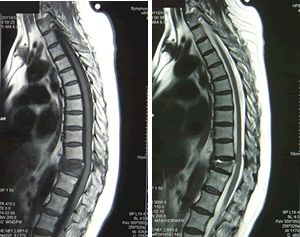

【問題点】

当日撮影されたMRIにて外形の圧壊についても所見が取れており、11級認定は堅かった。

(参考画像)

【立証ポイント】

痛みについてはどんどん回復していた為、きっちり半年で症状固定。症状固定時のレントゲンでも圧壊がはっきりわかる為、11級7号認定となった。